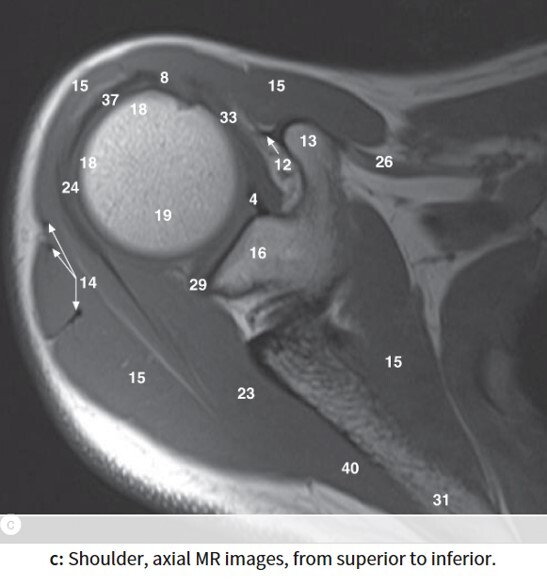

Label 16,18,19,23

16=Glenoid process of Rt. scapula

18=Greater tubercle of Rt. humerus

19=Head of rt. humerus

23=Rt. infraspinatus muscle

Label 13,15,16,18,19,23,32

13=Rt. coracoid process

15=Rt. deltoid muscle

23= Rt. infraspinatus muscle

32=Rt. subscapularis muscle